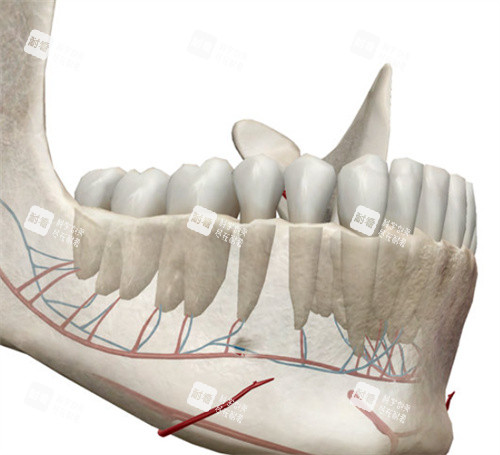

6. 下颌前部根尖下截骨术

主要用于矫正下颌前牙区的畸形,可以在保留牙齿的情况下移动下颌前部骨段。

手术特点:

手术范围较小。

修复较快。

适用于局部畸形矫正。

常与正畸治疗配合。